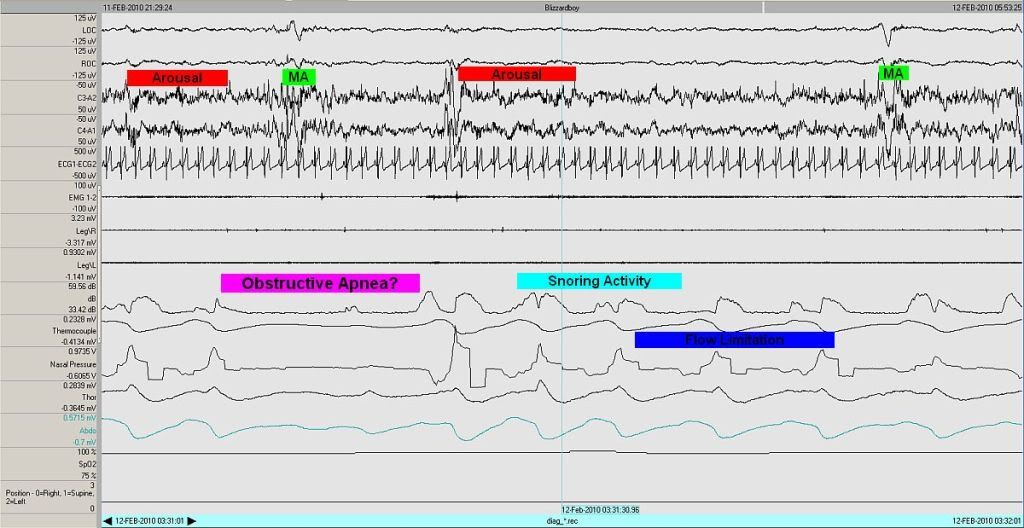

So anyway, having downscored most of the obstructive apneas, let's take a close-up view of one of the ones that remains:

Things that suggest this is obstructive in nature include the snoring and flow-limited nature of the surrounding breaths.

On the other hand, the arguements that this, too, has a heavy central flavor include:

- the abdominal and thoracic belts also decrease in intensity

- the event is post-arousal

- the effoct belts do not progressively increase to try to overcome obstruction